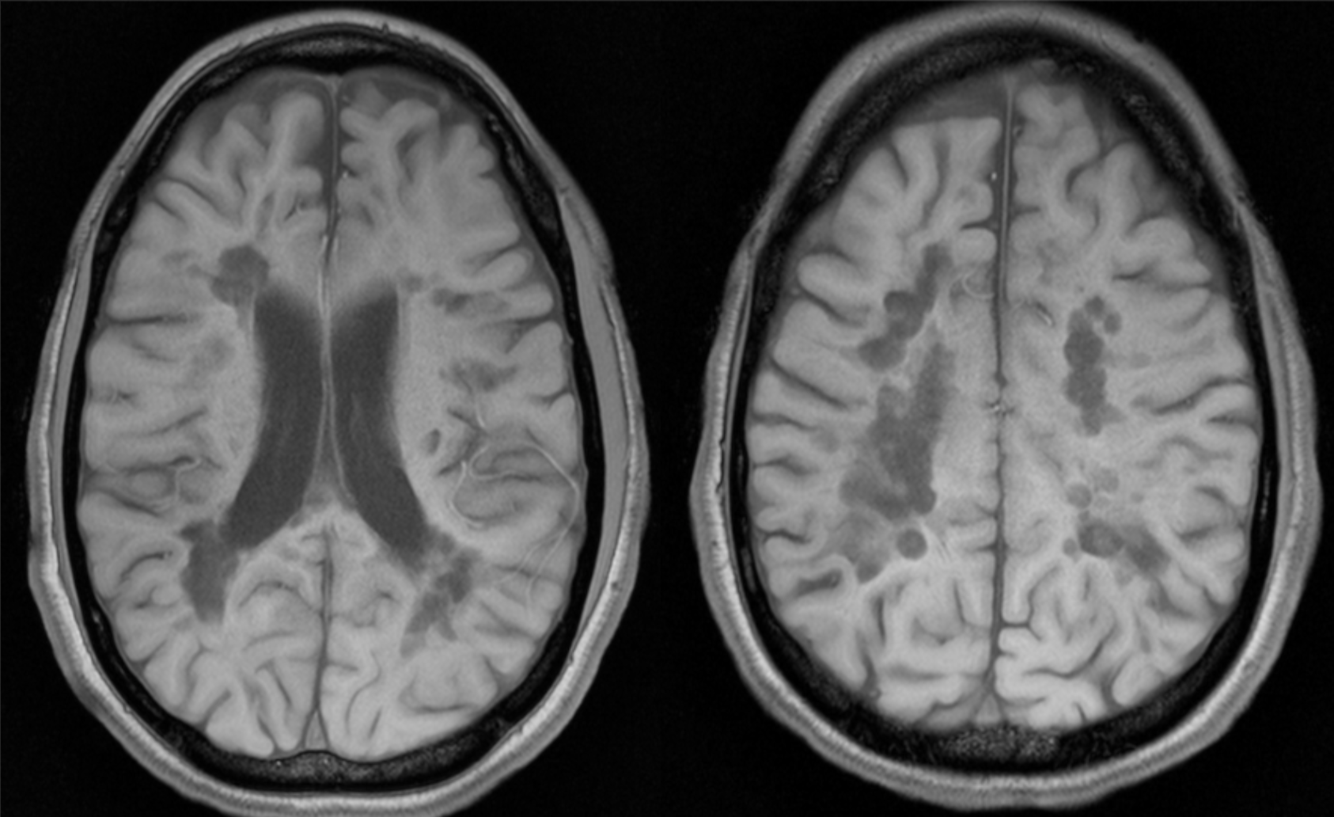

A 45 year-old female with cognitive impairment, ataxia.

Multiple sclerosis - black holes